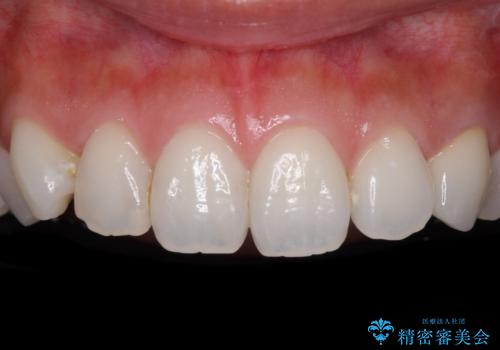

折れてしまって変色した前歯をオールセラミックに

仮歯装着の時点で自然な見た目となり、オールセラミッククラウンを装着した際には、まるで自分の歯のようと喜んでくださいました。

長年変色を気にしており、もっと早くに治療を行えば良かったとおっしゃっていました。